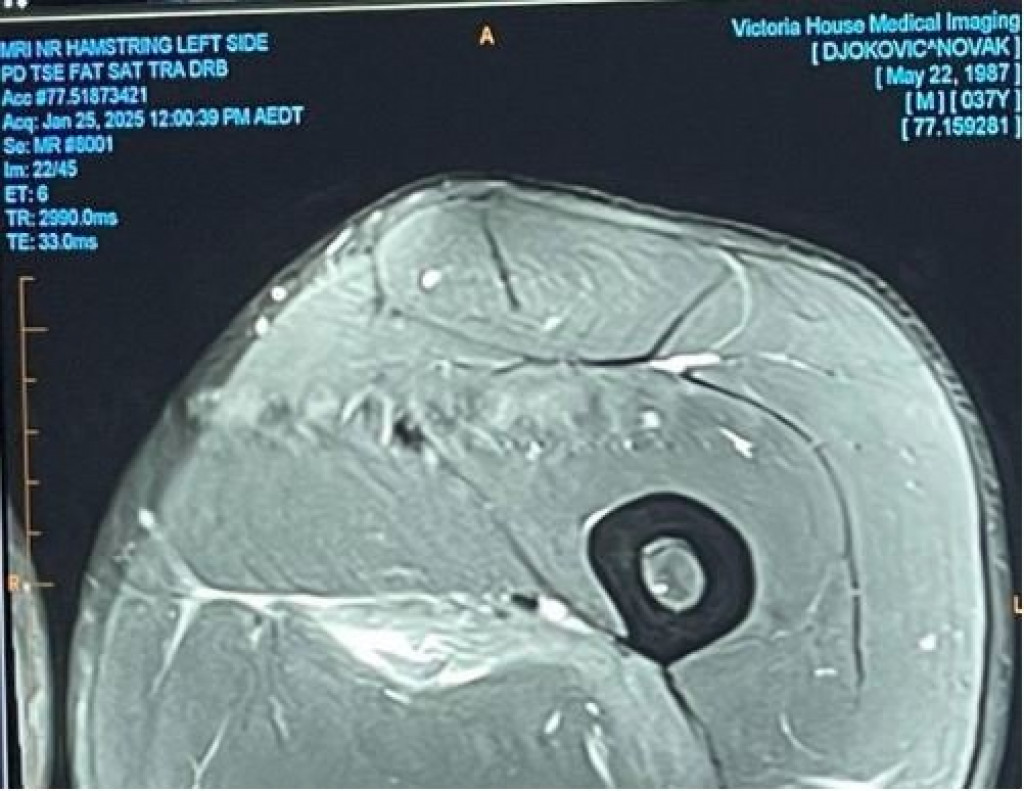

Novak Đoković odigrao je Australijan open s ozbiljnom povredom mišića, istegnućem, pa je na kraju predao Aleksanderu Zverevu polufinalni duel posle izgubljenog prvog seta. Tada su krenuli zvižduci, a mnogi su sebi dali za pravo da osporavaju da je Nole uopšte bio povređen, pa se on pravdao i objavljivao snimak magnetne rezonance. Da skanda,l bude veći, to su radili i Boris Beker i Džon Mekinro.